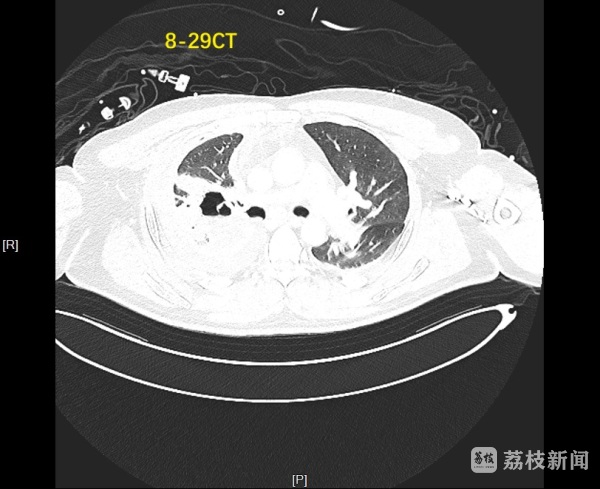

术后一周的CT复查显示,患者胸腔内气胸明显消失,上叶空洞显著缩小,顺利拔除引流管出院。术后一个月再次复查时,胸部CT证实右肺已完全复张,气胸症状彻底消失,达到临床治愈标准。